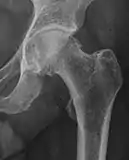

X-ray

Radiograph of a cam type impingement.

Projectional radiography ("X-ray")is often considered first line for FAI.[11] Anterior-posterior pelvis and a lateral image of the hip in question should be attained.[11] A 45-degree Dunn view is also recommended.[11][19]